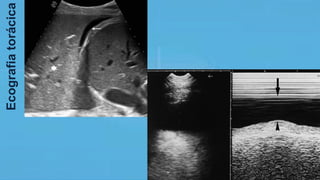

o Ecografia torácica: se disponível, treinamento de equipe para detecção

de pneumotórax, derrames pleurais e auxiliar no processo terapêutico.

Sugere-se o uso para estimar aeração alveolar em PAV, avaliação do

edema pulmonar, atelectasias e estimar recrutamento por PEEP